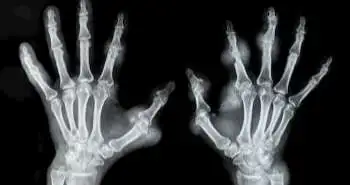

Adalimumab is a tumour necrosis factor (TNF) inhibitor involved to treat various types of arthritis states like ankylosing spondylitis and rheumatoid arthritis. It is the top-selling medication with $18 billion in sales in 2017 alone globally. The following license cessation of Adalimumab has glimpsed the emergence of the variously related biosimilar. The current study assessed the Adalimumab related biosimilars evidence in the treatment of rheumatoid arthritis (RA) from bio-originator trials to present context for critical review with relation to related biosimilars.